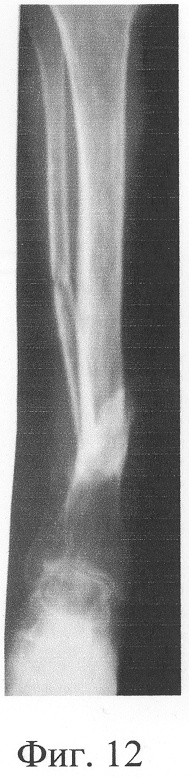

Больная П., 42 лет, поступила для оперативного лечения с диагнозом «атрофические ложные суставы обеих большеберцовых костей; сросшийся с укорочением 5 см перелом левой бедренной кости, хронический остеомиелит левой бедренной кости, фаза ремиссия; посттравматическая невропатия правого малоберцового нерва». В анамнезе – накостный, а затем дважды внеочаговый остеосинтез левой большеберцовой кости с исходом в ложный сустав; 4 операции внеочагового остеосинтеза правой большеберцовой кости, в том числе с костной пластикой; сроки фиксации в аппарате от 5 до 10 мес. Результат не достигнут: с обеих сторон сформировались ложные суставы (фиг.8-11 – клинические и фиг.12-15 – рентгенологические данные до лечения по предложенному методу).

Одномоментно выполнены операции: резекция ложных суставов обеих большеберцовых костей, резекция левой малоберцовой кости, комбинированный чрескостный остеосинтез костей обеих голеней, костная пластика ложных суставов деминерализованным костным аллотрансплантатом из трубчатой кости, предварительно в лабораторных условиях заселенным аутологичными мезенхимными стволовыми клетками, выделенными из костного мозга пациентки, с плотностью заселения 7-10 млн на 1 см3 трансплантата. В послеоперационном периоде потребовалась дополнительная коррекция положения фрагментов на правой голени, что привело к смещению трансплантата из костного паза. Дренажи удалены на 3-е сутки, швы сняты на 15 сутки, антибактериальная терапия под контролем клинического фармаколога с учетом анамнеза. Ходьба с дополнительными средствами опоры с 7 суток послеоперационного периода. Компенсация укорочения бедра обувью (фиг.16-17 – клинические и фиг.18-19 – рентгенологические данные в процессе лечения, трансплантаты отчетливо видны на рентгенограммах, отмечается нарастание плотности костной ткани в области трансплантатов).

Аппарат внешней фиксации с левой голени демонтирован через 3 месяца после операции при клинико-рентгенологической картине сращения перелома. Аппарат внешней фиксации с правой голени демонтирован через 7 месяцев после операции при клинико-рентгенологической картине сращения перелома (фиг.20-25 – результат лечения). При рентгенологическом и томографическом контроле в трансплантатах отмечалось постепенное нарастание плотности костной ткани с формированием костной мозоли на всем протяжении между трансплантатом и костными фрагментами (фиг.26-29 – динамика данных компьютерной томографии правой голени: отмечается нарастание плотности костной ткани в области трансплантатов и формирование регенерата между смещенным трансплантатом и костными фрагментами; фиг.30-33 – динамика данных компьютерной томографии левой голени: отмечается нарастание плотности костной ткани в области трансплантатов и формирование регенерата между трансплантатом и костными фрагментами).